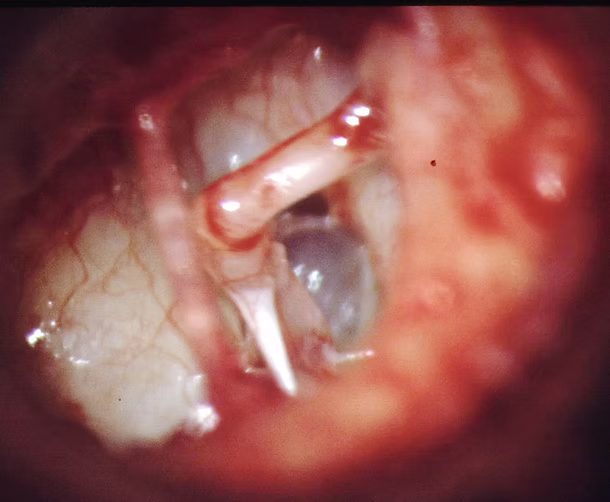

Foco otoesclerótico

La otoesclerosis inmoviliza la platina impidiendo el paso de la onda sonora al oído interno y produciendo pérdida auditiva.